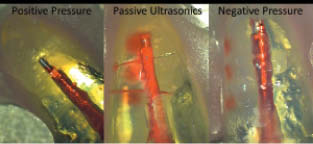

From Dentistry IQ – June 14, 2011 “Single file shaping of an entire root canal system may sound like a myth to some…… Nuff sed…Read more Related articles Endodontic Parousia – Nullius in Verba Redux (blogohj.oralhealthjournal.com) Drilling away at dental costs New website, new insurers’ approaches shake up market (blogohj.oralhealthjournal.com) And now for something uplifting … Read more